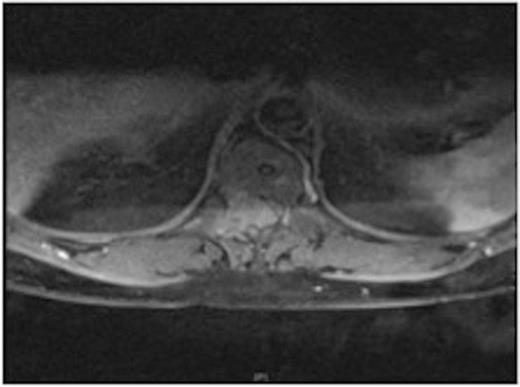

MRI showing the extra-dural tumour and extension into the soft tissue of the back

A one-year history of lower back pain, which was initially thought to be due to his liver metastasis, was investigated further with a full spine MRI scan. The scan revealed a large T10-11 extra-dural tumour with erosion of the T12 pedicle and extension into the soft tissue of the back. As a result of this discovery, the patient was referred for radiotherapy. Prior to commencement of this the oncologist requested a neurosurgical opinion from us.